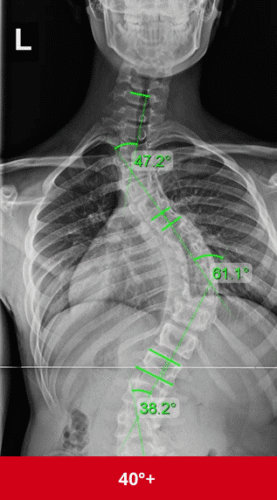

الانحناءات الأكبر من 45–50 درجة قد تستمر في الازدياد ببطء حتى بعد توقف النمو.

الانحناءات التي تبدأ بـ 20 درجة أو أكثر أكثر عرضة للزيادة مقارنة بالانحناءات الصغيرة.

الأشعة الدورية لقياس زاوية كوب هي الطريقة الوحيدة لمعرفة التطور.

هل جراحة اعوجاج العمود الفقري ضرورية؟

لا، نسبة كبيرة من الأطفال يتجنبون الجراحة عند التدخل المبكر، خاصة قبل الوصول لـ 40 درجة.